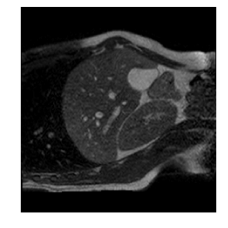

Qualitative results are shown in Fig. 4. We observe no large qualitative differences in the performances of MFIN and MFINc for either loss function. Since, MFINc-SSIM provides the best quantitative results, we show interpolated images from this method and compare them against SCIN-SSIM. Both methods perform well when the motion between the neighbouring images is low. This is reflected in the absence of any structures in the error images in Fig. 4.1. However, RMSE is lower for SCIN because it produces a denoised interpolated image, while MFIN carries over the noise pattern from the neighbouring known image. Whenever there exists high motion between the images being interpolated, SCIN produces blurry images and often misses image structures. This can be observed in cases 2-4 in Fig. 4. For all these cases, MFINc (and also MFIN) produces sharp images and largely preserves structures in the images. Fig. 4.2 shows a case where MFINc additionally has a much better performance with respect to image alignment. Fig. 4.3 shows a representative case, with small improvement in image alignment, yet worse RMSE and SSIM values for MFINc. Finally, Fig. 4.4 shows a case, where MFINc produces worse alignment of structures than SCIN.

Fig. 4 shows a comparison of a representative motion field predicted by MFINc with that computed via the GS registration algorithm. We can see that the motion field produced by MFINc is smooth and has sharper motion boundaries. The reason for this might be that the used registration is more regularized due to its parametric model, where motion is defined by a grid of control points with 4x4 pixel spacing and linearly interpolated in between. This might also explain the higher error in evaluation of the flow field predicted by the network over the whole image (RefMotErrFl) than only over the liver (RefMotErrFlLiver).

Figure 3: Ground truth images (a), SCIN-SSIM results (b) and difference images (c), MFINc-SSIM results (d) and difference images (e). Rows: (1) low motion case, (2)-(4) high motion cases, where MFINc produces (2) much better, (3) slightly better and (4) worse structure alignment that SCIN. (RMSE, SSIM) pairs are indicated over the respective errors images.